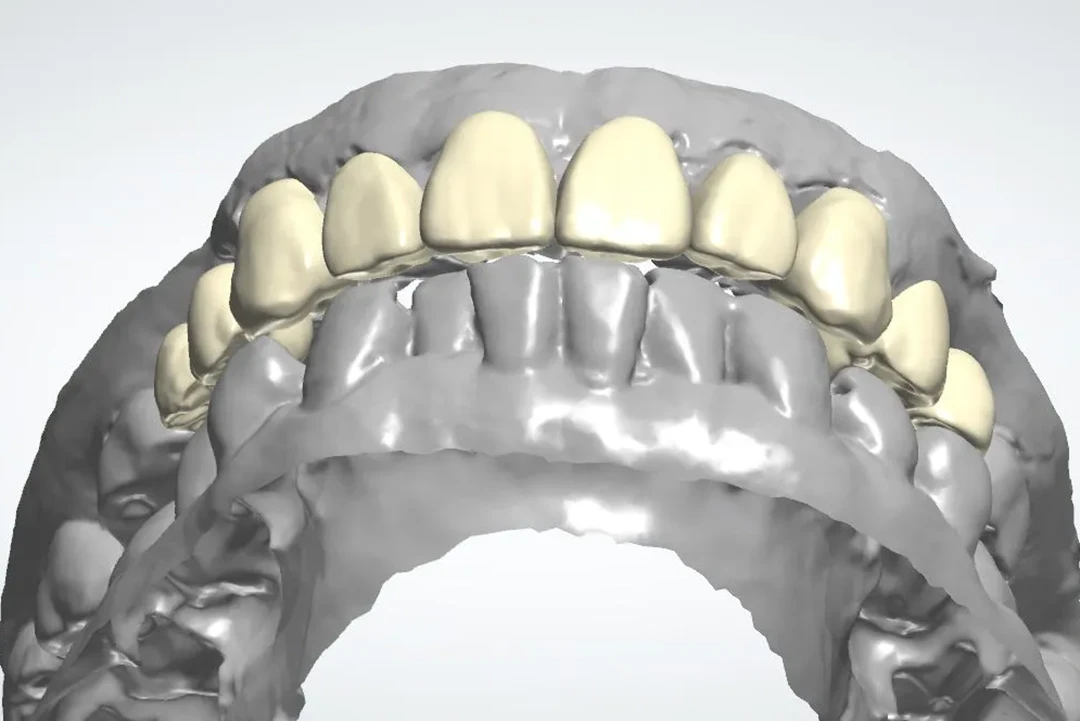

De 61 años nos visita con dientes dañados por caries y una prótesis antigua que ya no podía utilizar. Gracias a la planificación digital y la cirugía guiada, realizamos las extracciones y colocamos implantes con una prótesis fija el mismo día. Recuperó su sonrisa y la confianza de inmediato.